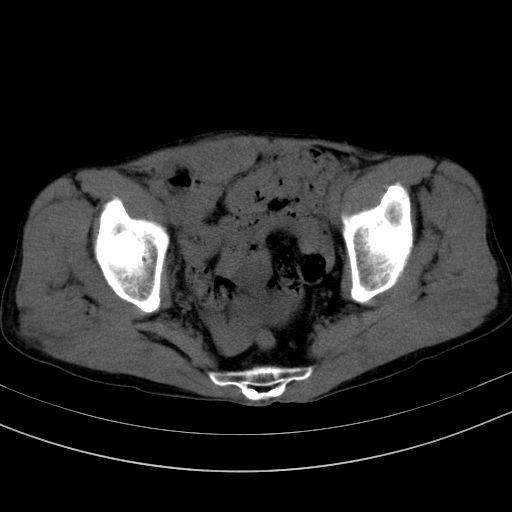

以下是引用37度在2010-1-9 14:37:00的发言:[br]1.双肾囊肿,左肾积水结石,.胆总管轻度扩张;[br]2.病灶在腹膜外,考虑纤维瘤。

以下是引用dyqct在2010-1-9 17:56:00的发言:[br]考虑:1.双肾囊肿,左肾积水结石、旋转不良。[br] 2.右侧腹直肌血肿或纤维瘤。[br]肠道准备不好。做个增强。